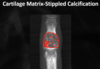

What is seen here in regards to density?

Osteoblastic (large zone of transition, ill defined)